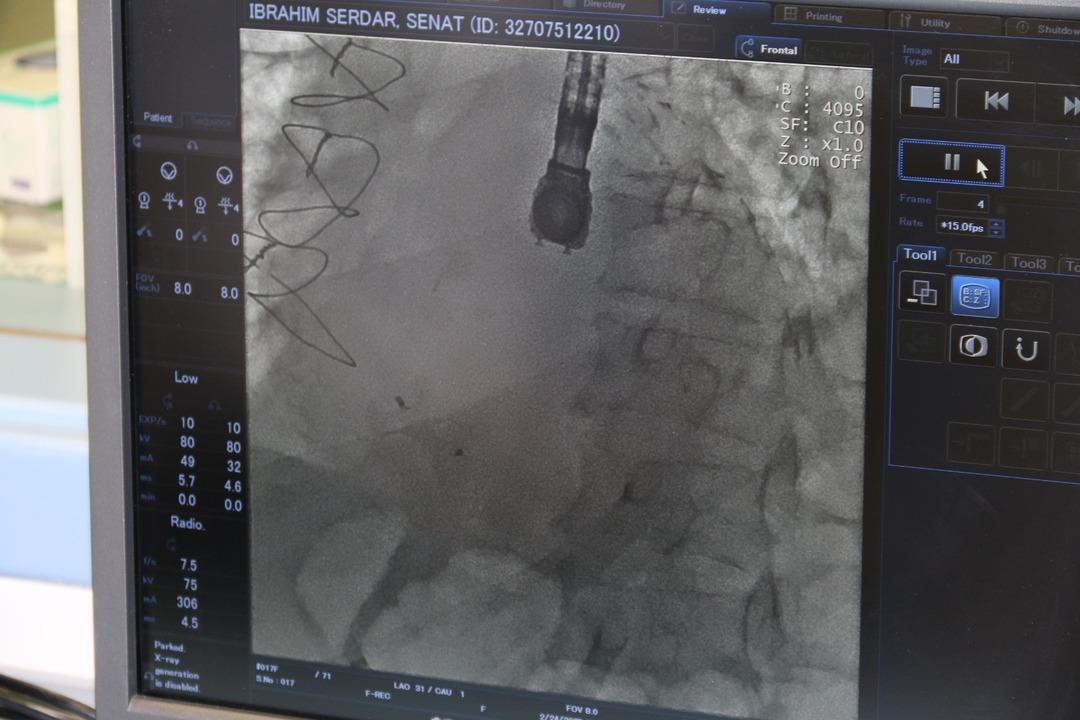

Operasyondan bahsetmişken, Eskişehir Hastanesi’nin kardiyoloji uzmanı Dr. Bekafaş Murat, “Hastamız, nefes eksikliği ve kalp yetmezliği belirtisi ile polikliniğimize başvurdu. Ama hastamızın tarihini aldığımızda, yaklaşık 20 gün önce başka bir merkezde kalp krizi geçirdiğini ve anjografi ile kalplerin kalbinin kalbinin kalbinin kalbinde tedavi edildiğini öğrendik. Bu normalde, bu hastalığın tedavisi için ilk aşamada ameliyat önerilir, ancak hastamızın ciddi çapraz bölge hastalıklarına sahip olması nedeniyle cerrahi prosedürün çok yüksek olduğuna karar verilmiştir.

Murat Kardiyoloji Uzmanı; Tabii ki, bu aşama çok zorlu bir aşamadır. Çünkü VSD dediğimiz delikle ilgilenmezsek, çoğu hasta maalesef ölüyor. Ek olarak, müdahale etsek bile, bu hastaların neredeyse yüzde 50-55’i hala ölebilir. Muhtemelen bu prosedürü Türkiye’de yapan 8-9 hasta, ancak 8-9 hasta var. Bu noktada, hastamız bu prosedürün ve yaşamın nadir örneklerinden biridir. Bu prosedür ilk olarak Eskişehir’de hastamıza yapıldı. Şu anda, hastamızın genel durumu iyidir; Deliği kapattıktan sonra hızlı bir kurtarma işlemi başladı, umarım bugün indirmeyi planlıyoruz. Bu hastalık tedavi edilmezse, hastaların neredeyse yüzde 94-96’sı bir ay içinde ölür. Bu hastalık cerrahi prosedür ile tedavi edilirse, maalesef yüzde 55’inin öldüğü durumlarda anjiyografiye giren kasıkların yüzde 45’i. Çok ciddi bir komplikasyon olabileceğinden, kişi kişinin kalp krizi geçirdiği anda ilk saatlerde teşhis ve tedavi edilmelidir. Böylece atlanabilir; Hastanın genel durumu kötüleşmeden fark edilemez veya fark edildiğinde acil tedavi uygun olmayabilir.